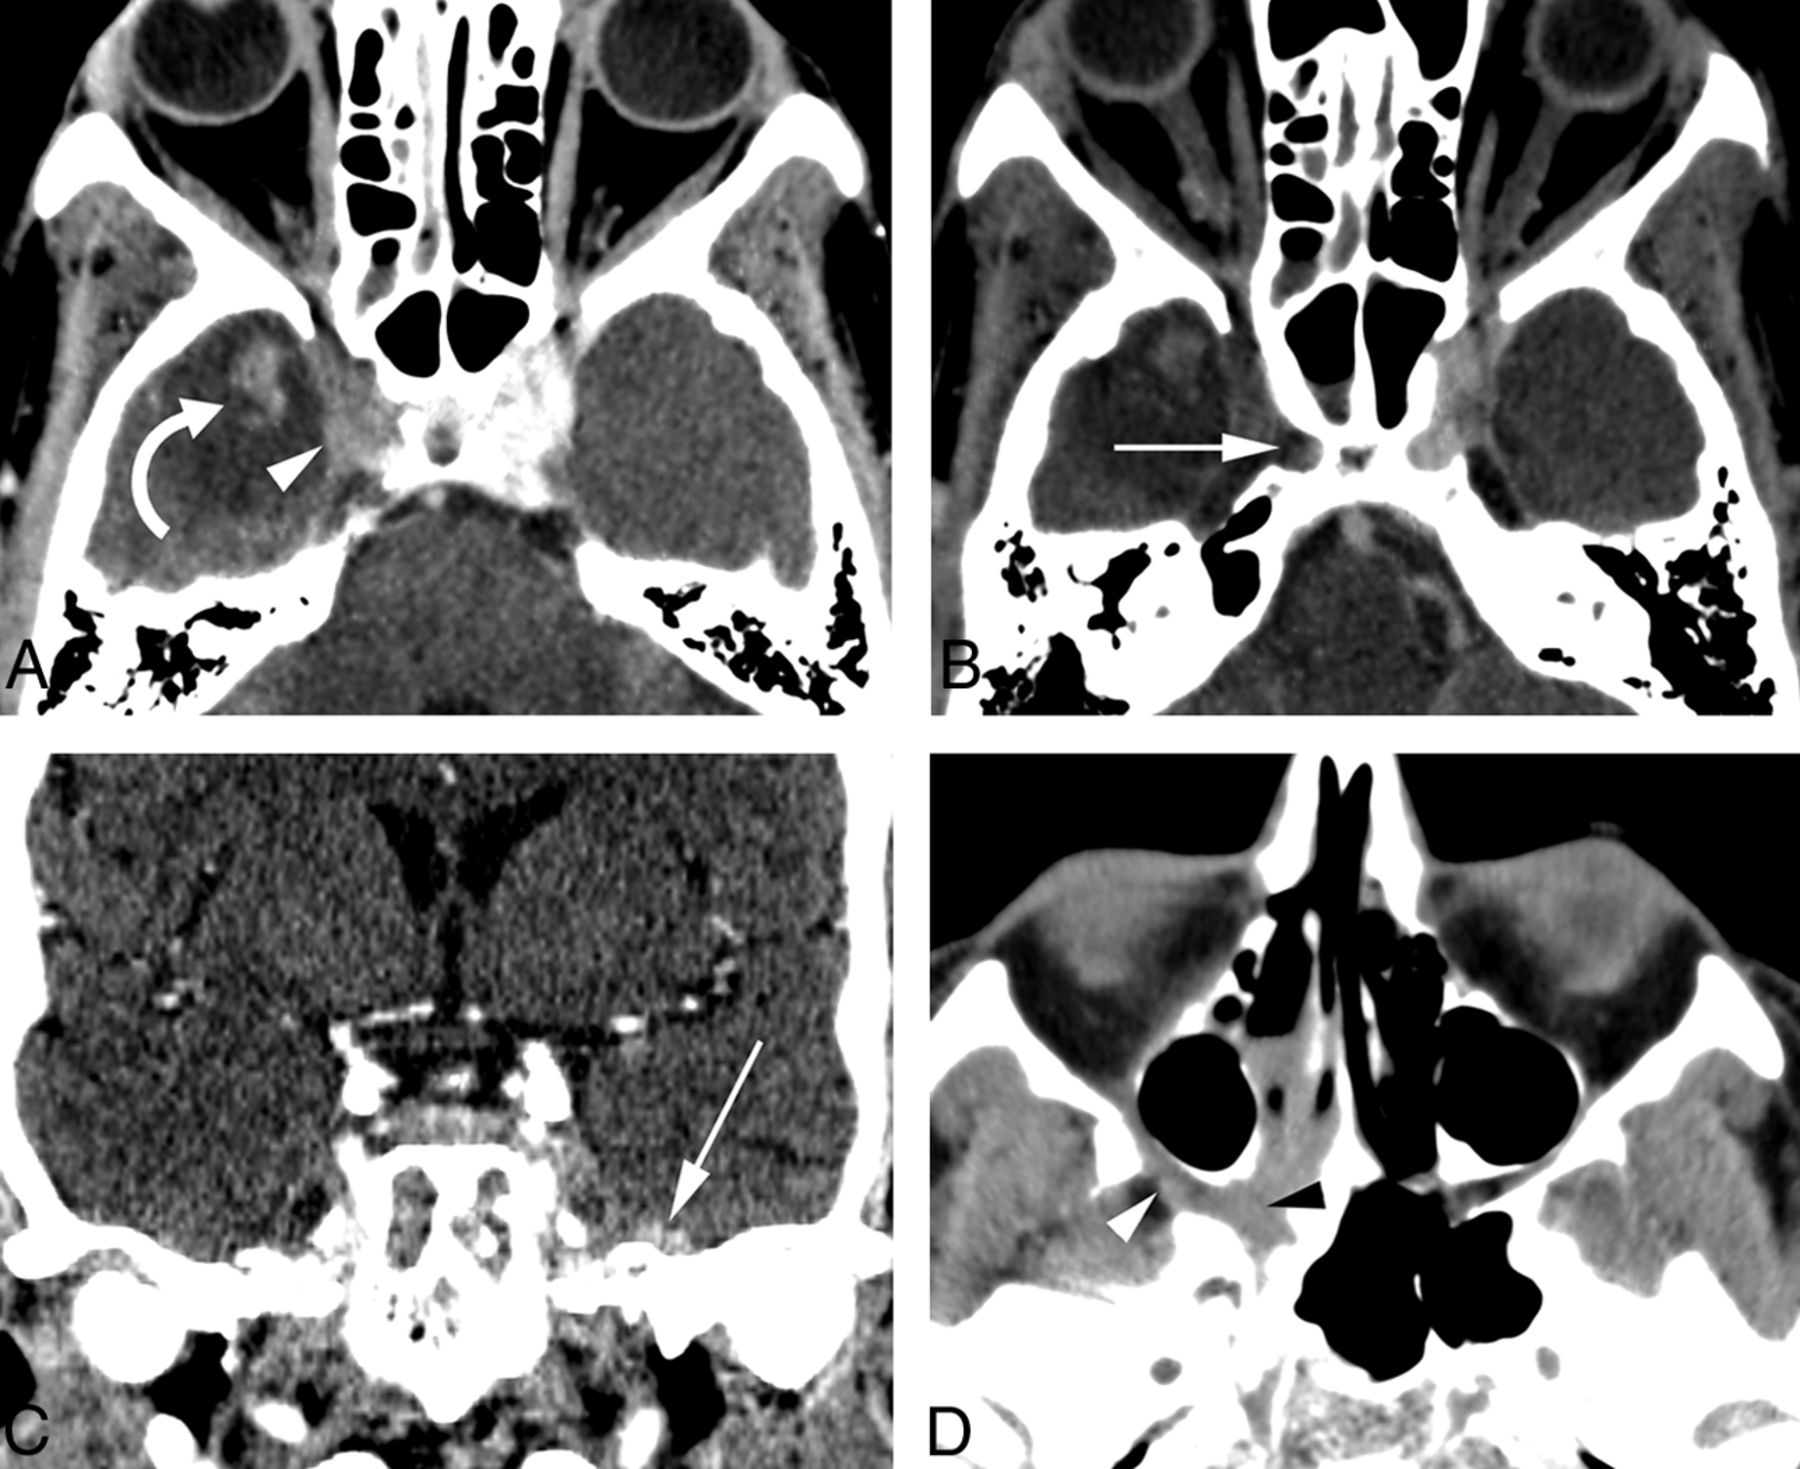

Thirteen variables had 100% specificity for AIFR, but only 5 of these had a sensitivity of >30% (nasolacrimal duct, lacrimal sac, septal ulceration, orbital involvement, and bone dehiscence; Figs 2 and 3). The remaining variables with 100% specificity represented late-stage disease findings (epidural, subdural, abscess, venous thrombosis, arterial thrombosis, cavernous sinus involvement, intraparenchymal extension, and horizontal palate involvement; Fig 4). Variables related to the degree of opacity had relatively poor sensitivity and specificity as binary variables.

Examples of advanced manifestations of AIFR. A and B, Axial postcontrast CT images show a filling defect in the right cavernous sinus (white arrowhead) with adjacent parenchymal hyperattenuation or focal area of enhancement (curved arrow) most consistent with an acute hemorrhagic infarction in the right anterior temporal pole or parenchymal involvement by AIFR, respectively. There is also partial thrombosis of the right internal carotid artery (white arrow). C, Postcontrast coronal CT in a different patient shows subtle left epidural thickening along the floor of the middle cranial fossa (white arrow). D, Axial noncontrast CT in a third patient shows soft-tissue infiltration of the right sphenopalatine foramen and pterygopalatine fossa (black arrowhead), with extension into the right orbital apex (white arrowhead).